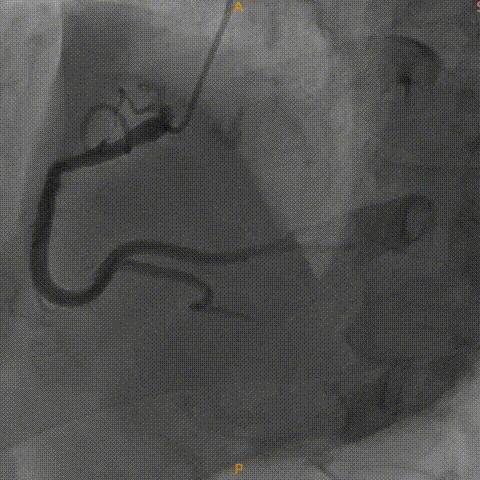

左冠造影灌注良好

右冠造影灌注良好

主动脉根部造影